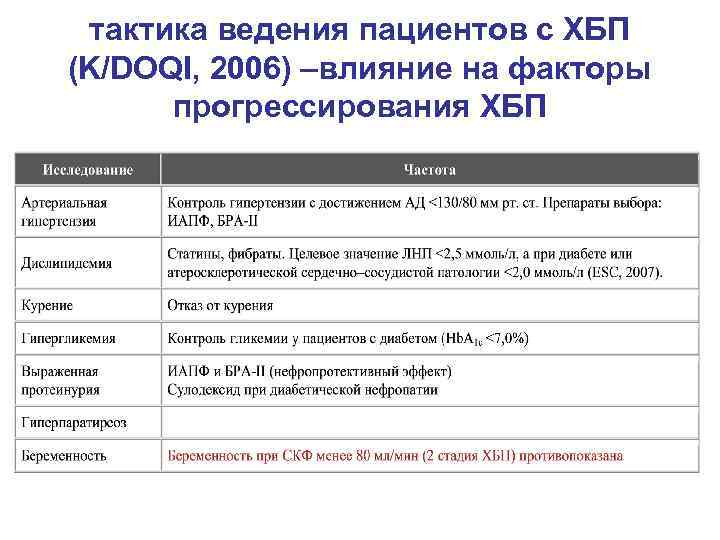

тактика ведения пациентов с ХБП (K/DOQI, 2006) –влияние на факторы прогрессирования ХБП

тактика ведения пациентов с ХБП (K/DOQI, 2006) –влияние на факторы прогрессирования ХБП